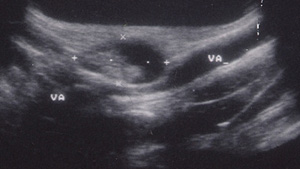

L'ecografia delle parti molli dell'ascella evidenzia pacchetto di linfonodi in fase colliquativa che comprime la vena ascellare.

Gli esami ematologici dimostrano: VES= 28 ,modesta leucocitosi neutrofila,, transaminasi normali, sierologia per EBV Toxo e citomegalovirus negativa , Mantoux negativa. Anticorpi antiBartonella IgG < 1:128. L'ecografia delle parti molli ascellari a destra descrive un pacchetto linfonodale composto da 5-6-linfonodi, di cui uno di dimensioni 20x30 mm, colliquato comprimente la vena ascellare.